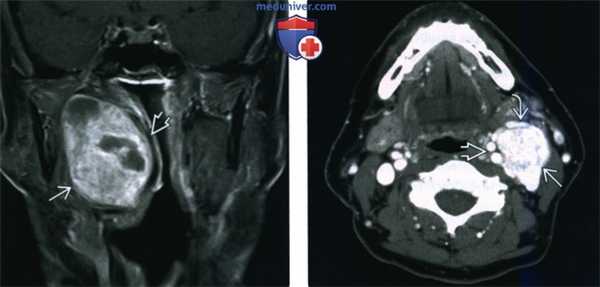

(Слева) МРТ Т1ВИ FS c КУ, коронарная проекция. В сонном пространстве определяется накапливающее контраст новообразование. В толще опухоли имеются участки кистозного перерождения, которые весьма характерны для шванном. Характерно смещение внутренней сонной артерии в медиальную сторону.

(Справа) КТ с КУ, аксиальная проекция. В надподъязычном отделе сонного пространства визуализируется шваннома, интенсивно накапливающая контраст. Внутренняя и наружная сонные артерии смещены в медиальную сторону, что характерно для шванном. Внутренняя яремная вена в редких случаях смещается кпереди. Если шваннома богато кровоснабжается, то по своему виду она может напоминать параганглиому.

(Слева) МРТ Т1ВИ FS c КУ, аксиальная проекция. В правом сонном пространстве визуализируется крупное новообразование, однородно накапливающее контрастное вещество. Такой облик опухоли весьма характерен для шванномы. Шванномы данной локализации могут происходить из ЧН IX-XII. Чаще всего встречаются шванномы блуждающего нерва.

(Справа) КТ в костном окне, аксиальная проекция. Фестончатые изменения костных структур в области ската характерны для шванном. Шваннома, локализующаяся в носоглоточном отделе сонного пространства, может ремоделировать костную ткань основания черепа. Для параганглиом, напротив, характерен деструктивный рост.

(Слева) КТ с КУ, аксиальная проекция. В сонном пространстве, сразу над подъязычной костью, определяется шваннома, преимущественно кистозного строения. Для крупных опухолей весьма типично наличие кист. Обратите внимание на редкие кальцификаты в передней стенке опухоли.

(Справа) МРТ Т1ВИ, аксиальная проекция. Крупная опухоль сонного пространства, которая смещает сонные артерии вперед и в медиальную сторону, а внутреннюю яремную вену - назад и в латеральную сторону. Интраоперационно было установлено, что опухоль происходит из периферического нерва и является злокачественной.